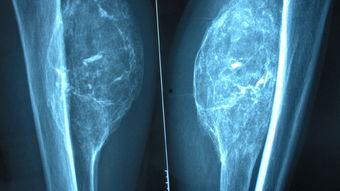

颌面手术,顾名思义,就是针对面部骨骼和软组织的手术。它可以是矫正牙齿、修复面部创伤,甚至是改善面部轮廓。这些手术不仅需要高超的医术,还需要医生们对解剖学的深刻理解。

随着互联网的普及,越来越多的颌面手术视频出现在我们的视野中。这些视频不仅让我们看到了手术的全过程,还让我们对颌面手术有了更直观的了解。